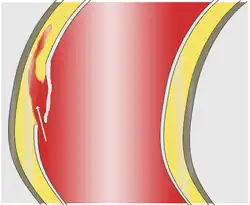

Blood penetrates the intima and enters the media layer.

As with all other arteries, the aorta is made up of three layers, the intima, the media, and the adventitia. The intima is in direct contact with the blood inside the vessel, and mainly consists of a layer of endothelial cells on a basement membrane; the media contains connective and muscle tissue, and the vessel is protected on the outside by the adventitia, comprising connective tissue.[26]

In an aortic dissection, blood penetrates the intima and enters the media layer. The high pressure rips the tissue of the media apart along the laminated plane splitting the inner two-thirds and the outer one-third of the media apart.[27] This can propagate along the length of the aorta for a variable distance forward or backward. Dissections that propagate towards the iliac bifurcation (with the flow of blood) are called anterograde dissections and those that propagate towards the aortic root (opposite of the flow of blood) are called retrograde dissections. The initial tear is usually within 100 mm of the aortic valve, so a retrograde dissection can easily compromise the pericardium leading to a hemopericardium. Anterograde dissections may propagate all the way to the iliac bifurcation of the aorta, rupture the aortic wall, or recanalize into the intravascular lumen leading to a double-barrel aorta. The double-barrel aorta relieves the pressure of blood flow and reduces the risk of rupture. Rupture leads to hemorrhaging into a body cavity, and prognosis depends on the area of rupture. Retroperitoneal and pericardial ruptures are both possible.[28]

The initiating event in aortic dissection is a tear in the intimal lining of the aorta. Due to the high pressures in the aorta, blood enters the media at the point of the tear. The force of the blood entering the media causes the tear to extend. It may extend proximally (closer to the heart) or distally (away from the heart) or both. The blood travels through the media, creating a false lumen (the true lumen is the normal conduit of blood in the aorta). Separating the false lumen from the true lumen is a layer of intimal tissue known as the intimal flap.